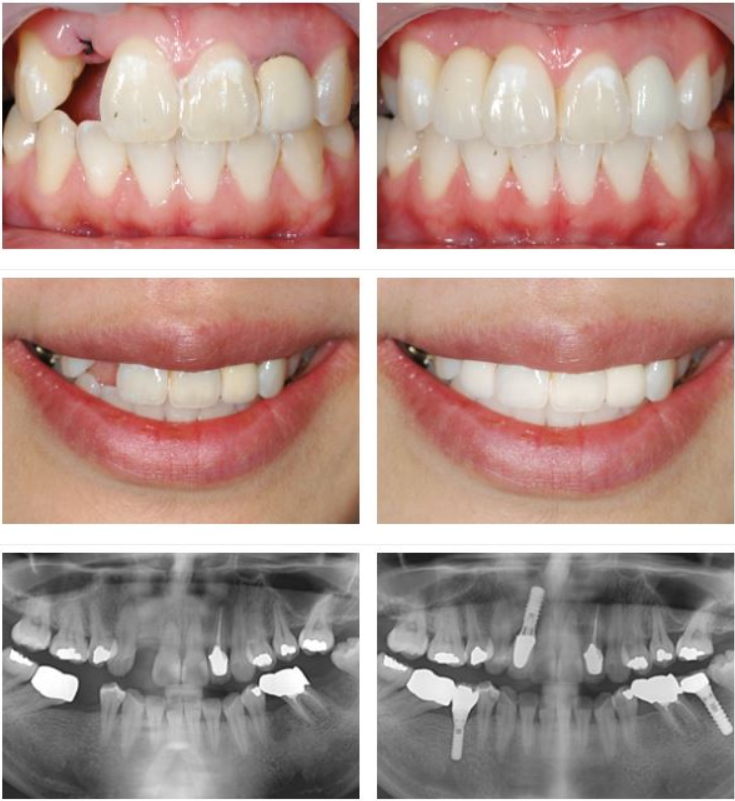

지르코니아는 금속 성분이 없는 세라믹 재료로, 자연치아와 유사한 색상과 투명도를 가진 것이 특징이라고 합니다. 잇몸이 내려가더라도 금속 테두리가 드러나지 않아 심미성이 뛰어나고 내구성도 우수한 편이라고 알려져 있습니다. 특히 앞니 임플란트의 경우 자연스러운 미소를 되찾는 데 도움이 될 수 있습니다.